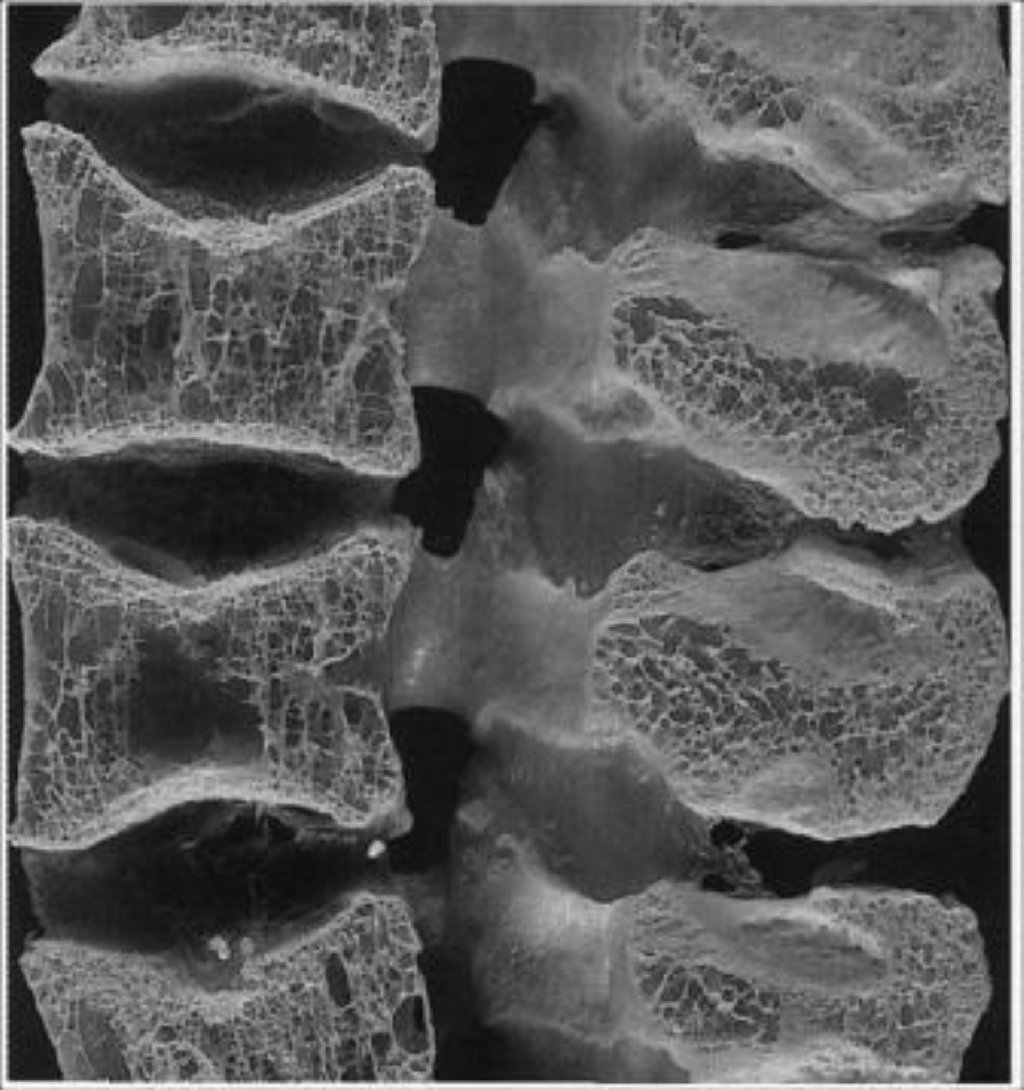

Osteoporozun əsas səbəbləri aşağıdakılardır: Yaşlanma: Yaşlanma prosesi ilə birlikdə, sümüklərin ...

Osteoporozun əsas səbəbləri arasında yaşlanma, hormonal dəyişikliklər, genetik faktorlar, vitamin və ...

Osteoporozun Səbəbləri Yaşlanma: Yaş ilə birlikdə sümük kütləsi tədricən azalır. Hormonal Dəyi ...